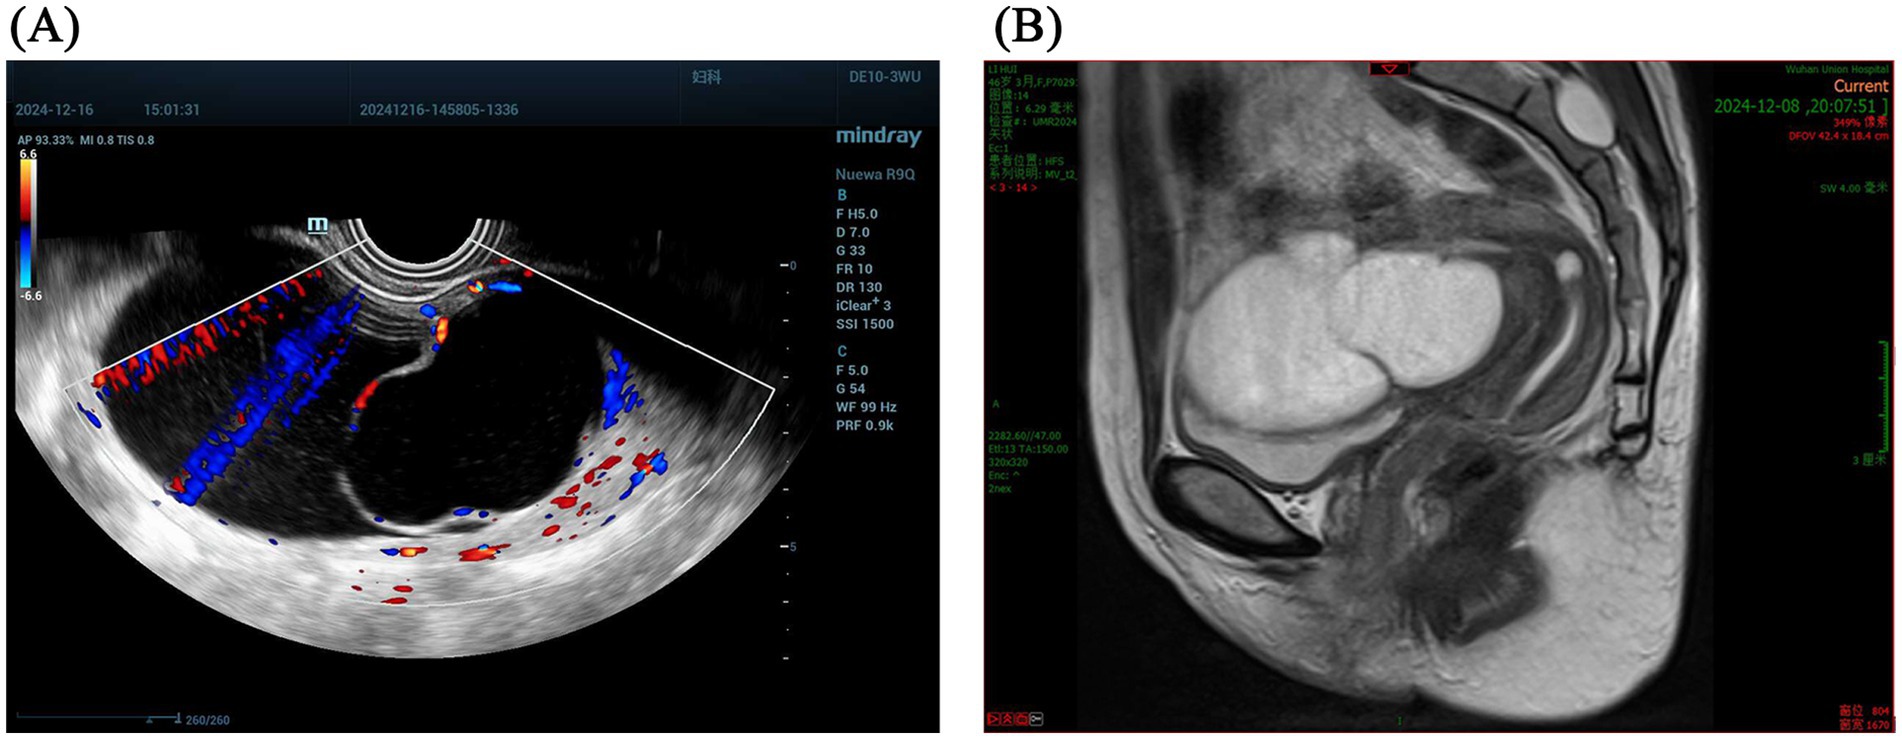

Serum tumor markers, including CA125, CA19-9, CEA, and AFP, showed no specific abnormalities. Transvaginal color Doppler ultrasound identified a hypoechoic mass measuring approximately 90 × 75 mm in the anterior uterine corpus, characterized by well-defined margins and internal septations, with Doppler imaging showing blood flow within the mass (Figure 1A). Pelvic MRI confirmed the presence of a cystic structure in the anterior part of the uterine corpus, showing hyperintensity on T2 imaging and mild enhancement along its periphery (Figure 1B).

Figure 1. (A) Transvagina1 color Doppler ultrasound identified a hypoechoic mass characterized by well-defined margins and internal septations, with Doppler imaging showing blood flow. (B) Pelvic MRI confirmed the presence of a cystic structure in the anterior part of the uterine corpus.